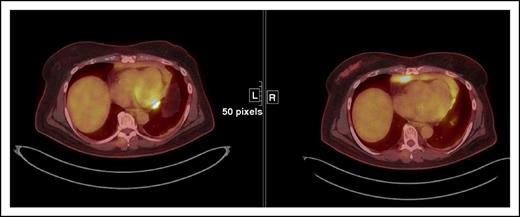

Restaging FDG-PET/CT and contrast-enhanced CT at 19 weeks demonstrates interval resolution of FDG uptake in a liver lesion. Restaging contrast-enhanced CT shows interval decrease in size of the hepatic lesion (arrow). Because the lesion did not disappear, this patient achieved a PR by immune-related response criteria, whereas the absence of FDG uptake on FDG-PET/CT is a CR by the Lugano Classification. There was also a complete metabolic response in the mediastinum and right upper abdomen (asterisks).